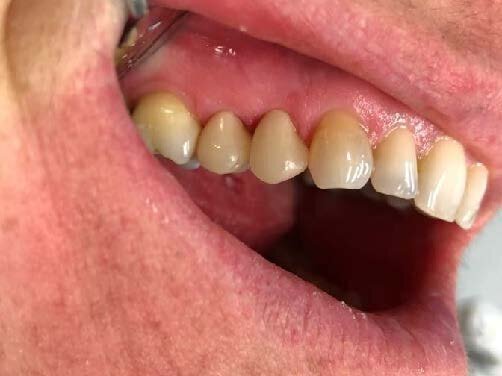

Fig. 1: Teeth preparation

A 52-year-old woman came to my practice due to acute pain in the region of the first quadrant. After a careful, intraoral and radiographic objective examination, we diagnosed destructive caries of teeth 14 and 15.

In the first instance, we performed root canal treatment of the teeth and consequently reconstructed both of them with Fiberglass Posts and covered them with ceramics manufactured with FONA MyCrown CAD/CAM system.

After the shoulder preparation, we moved on the treatment with MyCrown. Thus, an OptraGate-type dam was positioned in the mouth of the patient and some dry tips were used in order to control the salivation coming from the Steno Duct.